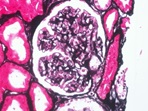

病理組織切片檢查

將組織經脫水浸蠟後,以石臘包埋後切成顯微薄切片,脫臘後以H&E染色,以供病理診斷。